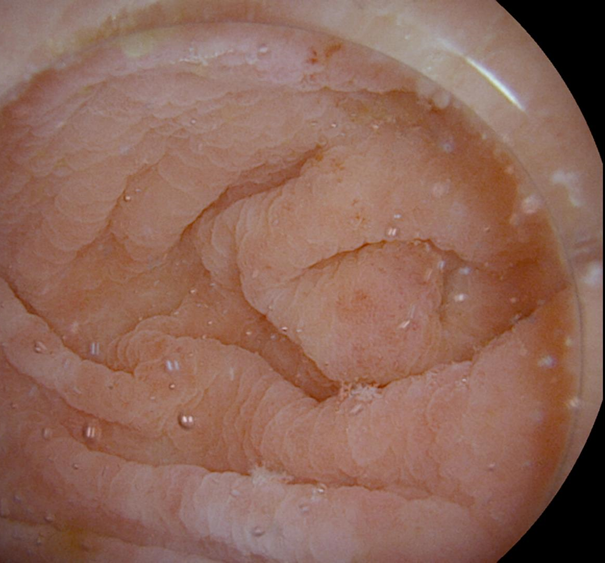

• La coloscopie à l’eau, en particulier en water exchange, vise à laver et aspirer en continu le côlon lors de la progression, remplaçant ainsi l’air et les résidus par de l’eau propre. Le principe est de progresser dans un côlon totalement immergé, et surtout non distendu, jusqu’au cæcum. L’insufflation n’est utilisée qu’au retrait, pour l’analyse des parois du côlon. Cette technique facilite l’examen, améliore le confort des patients, augmente la sécurité et améliore la performance diagnostique, avec un gain jusqu’à 10 % du taux de TDA selon les dernières méta-analyses. Au regard de ces résultats et surtout de sa facilité d’application sans surcoût, elle s’est imposée comme la méthode de référence.